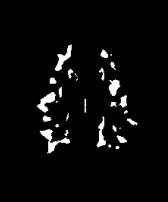

The white matter lesions in a total of 15 subjects were manually delineated by a neuroradiologist to be used as ground truth lesion segmentations for evaluation of the proposed method. We compared the proposed method with three state-of-the-art segmentation methods: 1) A supervised tissue segmentation developed for the AGES-Reykjavik data set, created with an artificial neural network classifier in the four dimensional intensity space defined by FLAIR, T1-w, T2-w and Proton Density weighted images and trained on 11 manually annotated subjects[12]; 2) the patch-based Subject Specific Sparse Dictionary Learning (S3DL) method [19], which takes FLAIR and T1-weighted images as input for lesion segmentation as well as three manually annotated atlases; and 3) the whole brain segmentation method FreeSurfer [17], which only takes a T1-weighted image as input, but is included in the comparison due to its widespread use. For each of the methods above, the preprocessing steps were as described in their associated publications. A visual comparison of the methods is shown for two subjects in Figure 2. The top row in Figure 2 demonstrates that SegAE can accurately segment lesion boundaries of the test image with the largest lesion load. The bottom row shows an example of a subject with a smaller lesion load but with enlarged ventricles.

| FLAIR image | Supervised | FreeSurfer | S3DL | SegAE | Manual |

|---|---|---|---|---|---|

![]() |